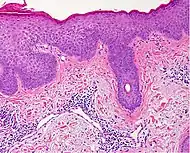

Spongiotic dermatitis

It is characterized by epithelial intercellular edema.[2]